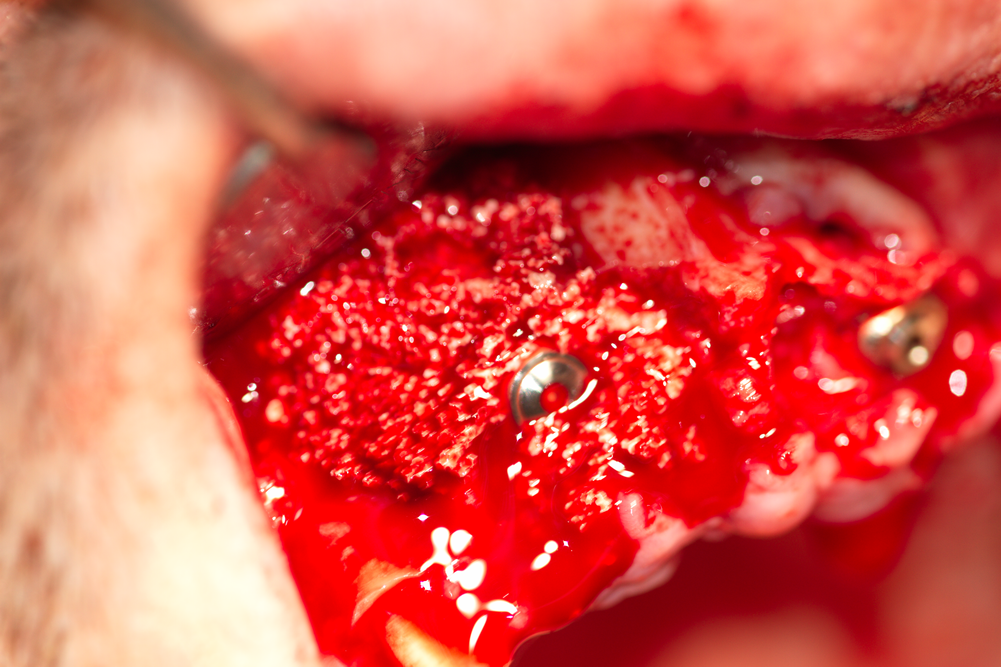

Два зъбни импланта във фронталния участък на горна челюст. Доста посетители на нашия сайт се плашат и понякога дори се ужасяват от кървавите снимки, но всъщност наличието на добро кръвоснабдяване в случая е белег за добра прогноза на лечението с импланти и в този случай се очаква добър оздравителен процес. Обратно, липсата на кървене означава атрофия на челюстната кост, съответно е предпоставка за забавен и усложнен оздравителен процес.